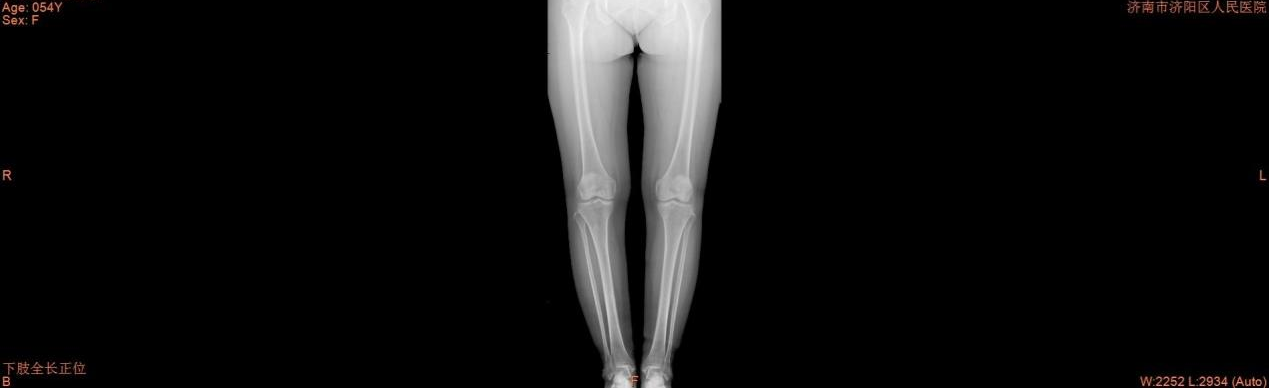

术前

54岁的赵女士,因右膝部疼痛1年余,加重2个月于2月19日住入我院骨一科。入院后,完善相关辅助检查,诊断为单侧膝关节骨性关节病、半月板撕裂,患者膝关节退行性变较轻,内侧间室疼痛明显,董孟政主任医师及张琦医师经过细致查体、阅片后决定保膝治疗,行膝关节半月板成形、胫骨高位截骨。